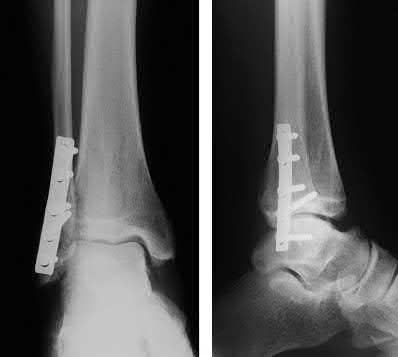

A 64-year-old woman is thrown off a horse, sustaining the injury shown in Figures A and B. She undergoes surgical fixation as seen in Figures C through E. What is the most commonly reported complication of this procedure?

The patient in the scenario has a 2-part proximal humerus fracture treated with a locking plate as seen in Figures A-E. The most common complication with the use of this implant is screw penetration. The terms screw cut out and penetration are often used interchangeably in the literature with cut out appearing more frequently in reports regarding intertrochanteric fractures.

Owsley et al retrospectively reviewed 53 proximal humerus fractures treated with locking plates and the same post-operative protocol. The most common complication was screw cut out or penetration, followed by varus displacement. They concluded that 3 and 4-part fractures in patients over 60 years have a higher incidence of failure.

Agudelo et al retrospectively reviewed 153 patients at a level-one trauma center treated with proximal humerus locking plates, investigating modes of failure for the implant. They determined that varus malreduction (head-shaft angle